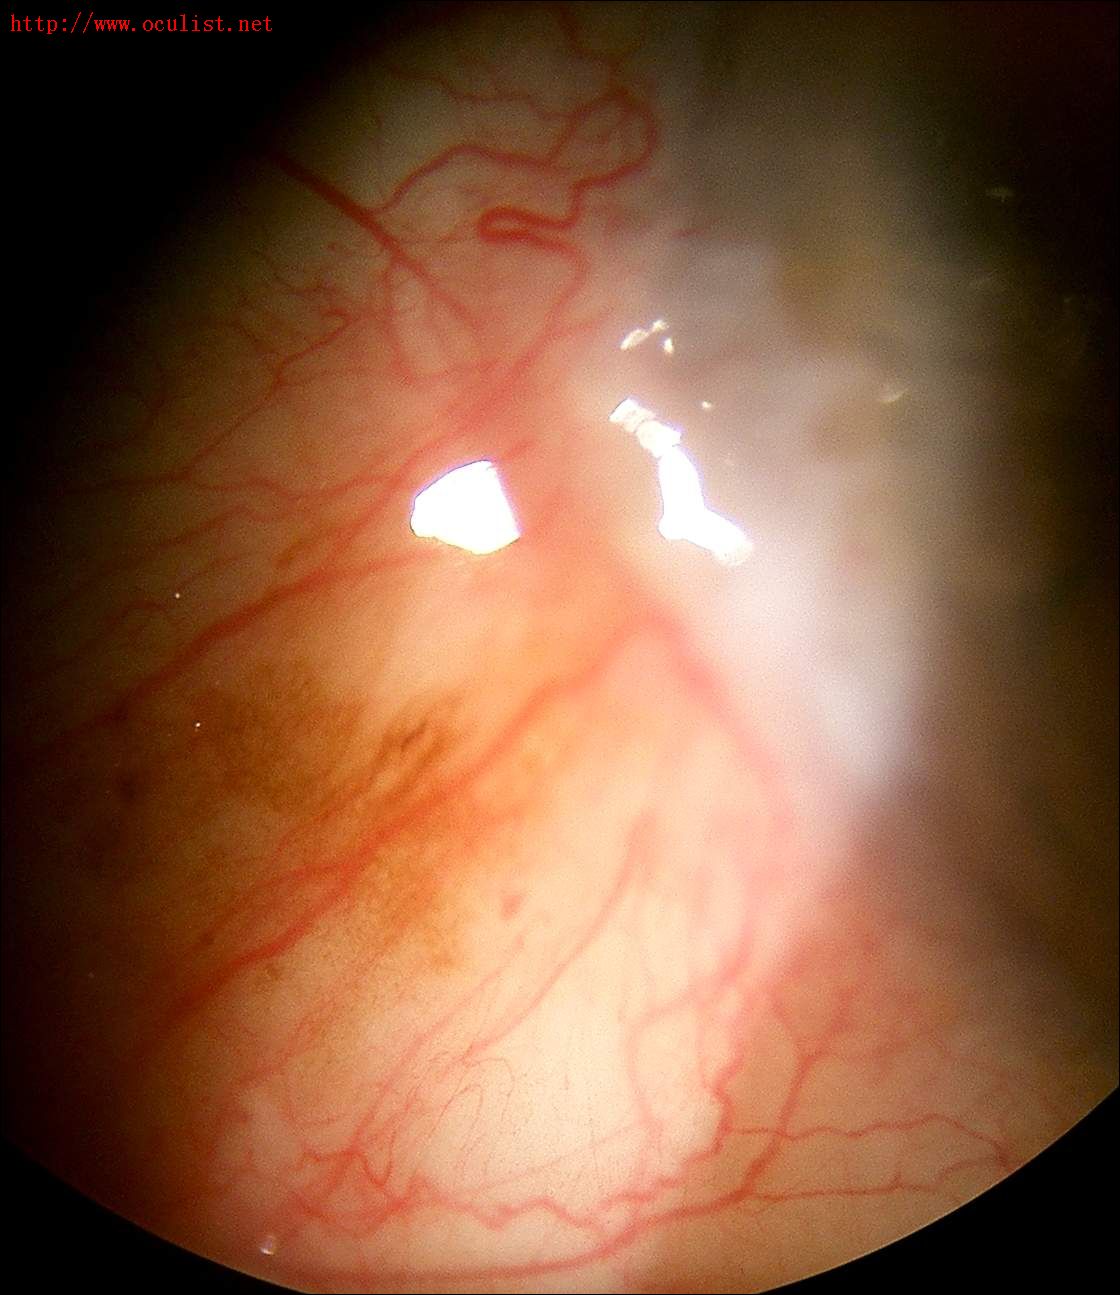

只是使用普通的数码相机就可以拍到裂隙灯下的漂亮照片!

2,拍KP,晶状体,虹膜缺损不需要加辅助光;拍眼表需要用手电在旁边照着眼睛。

数码相机拍摄的裂隙灯照片